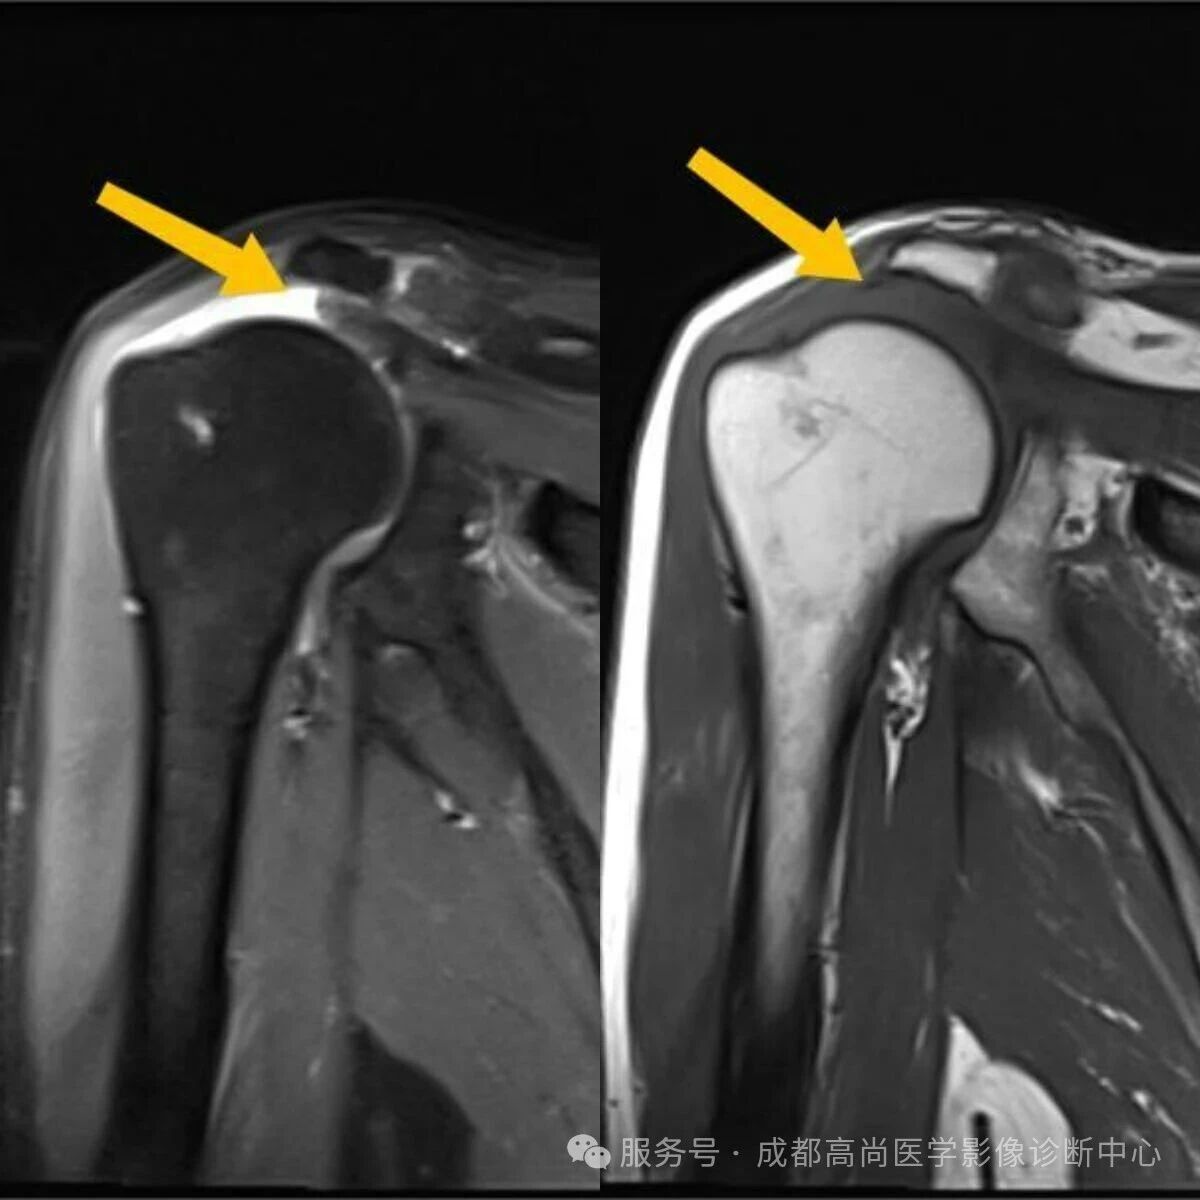

右肩 MRI 检查图像

图 1—5 MRI 平扫示右肩冈上肌肌腱失去正常形态结构,局部显示欠连续,肌腱附着点未见正常结构显示,提示冈上肌腱断裂。